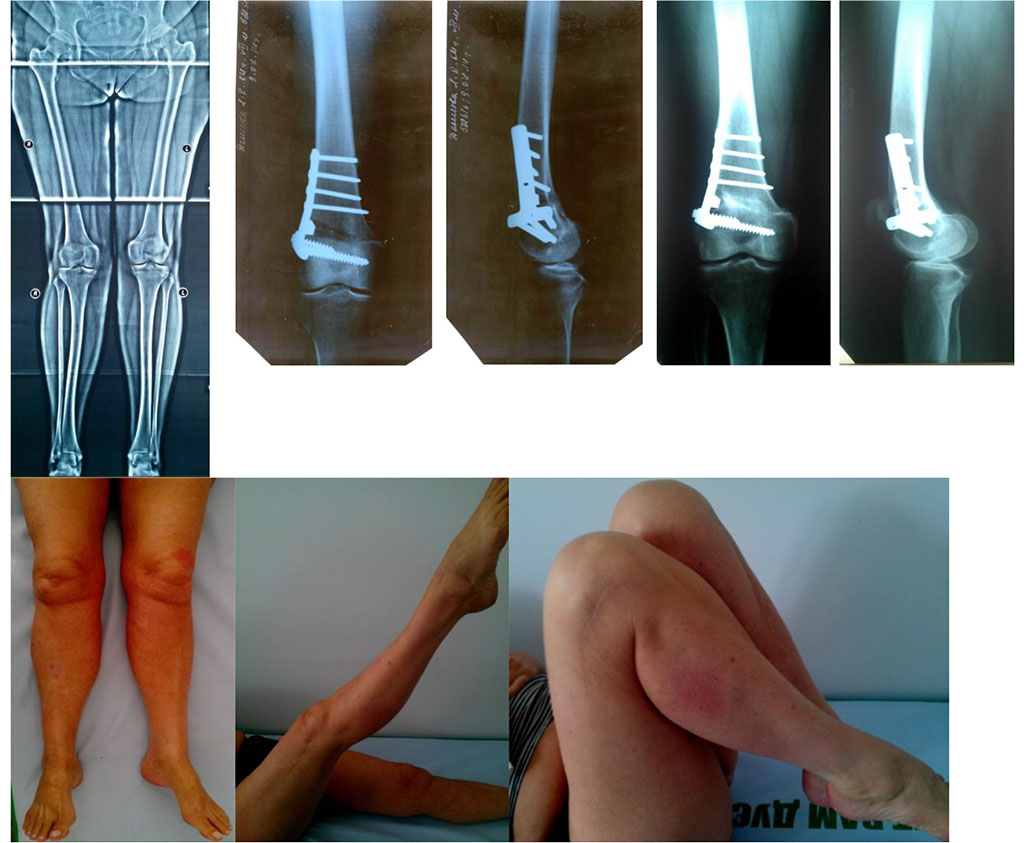

Figure 1.

Figure 1. X-ray images of the knee before and after surgery. Functions of the right lower limb 18 months later.

Diagnosis: bilateral gonarthrosis, 2-3 stage, with a values deformity of the right knee joint; degenerative damage to both meniscuses of the right knee.

The patient claimed for pain in her right knee; she admits herself ill over five years. From time to time, she got conservative treatment and sanatorium and spa, although without significant improvement.

The patient obtained an arthroscopic revision to her knee, debridement, corrective osteotomy of the femur, and metal osteosynthesis with a T-shaped plate. Eighteen months later, she expressed no claims, the range of motions in her knee was full, and we extracted the metal fixators. The result of the treatment was excellent (KSS – 86).